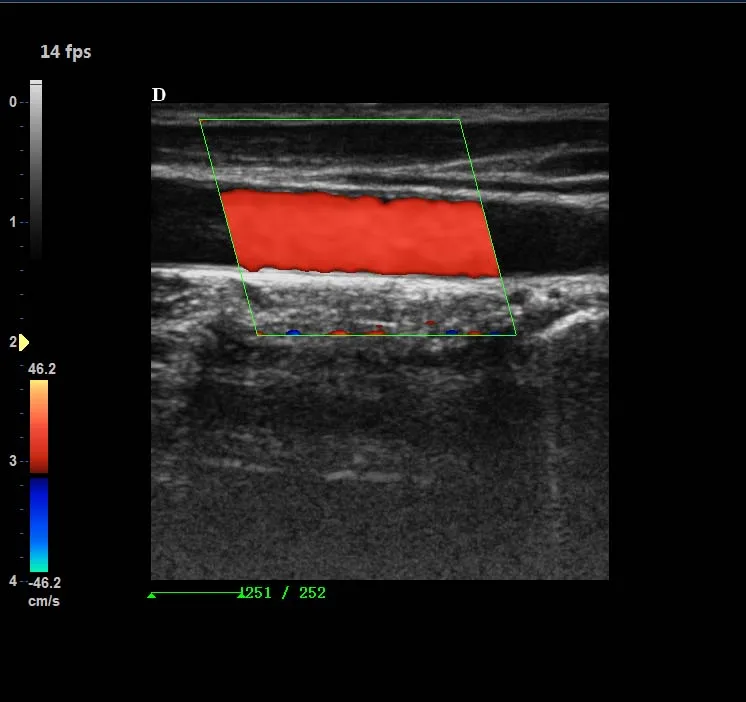

Operating Mode | B, 2B, 4B, B/M, M, B/C/D, B/D, CW, PW, velocity, power(direction), histogram, triples/duplex etc. |

Optional Configuration | 6.5Mhz R10 trans-vaginal probe 7.5Mhz linear probe 2.5Mhz phased array probe Elastography Any Printer |

Professional measurement software packages | Obstetric measurement Andrology measurement Gynecological measurement Urology measurement Peripheral vascular measurement Multiple births measurement Small organ measurement Orthopedic measurement Cardiac measurement |